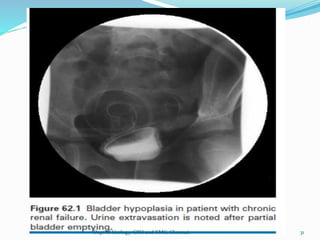

ANOMALIES IN SIZE

1.HYPOPLASIA:

-indicates small or tiny bladder

-usually seen in infants with sacral

agenesis

-children of diabetic mother

Occurs in

1.Hypospadias

2.B/L Renal agenesis

3.Infantile polycystic disease

30